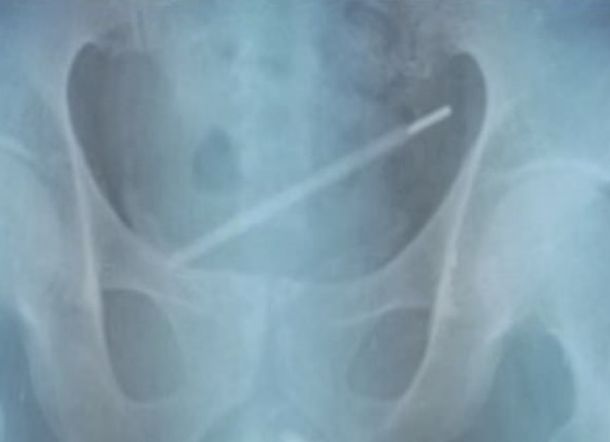

HARIANRIAU.CO - Seorang pria di China berakhir di rumah sakit setelah memasukkan termometer kaca ke dalam alat kelaminnya, dan itu berakhir di kandung kemihnya.

Apa yang dialami pria berusia 25 tahun ini dirinci dalam laporan kasus Urology Case Reports.

Dokter mengatakan bahwa pasien itu berasal dari Shanghai. Dia datang ke Rumah Sakit Tongren setelah melihat darah di urinnya.

Dia mengakui kepada dokter bahwa dia telah memasukkan termometer ke dalam uretra 11 hari sebelumnya.

Para dokter memasukkan cystoscope, tabung tipis yang dilengkapi kamera ke dalam uretra pria itu untuk melihat di mana termometer itu.

Diperkirakan bahwa alat itu mencapai kandung kemih pasien, karena kontraksi setiap kali ia buang air kecil.